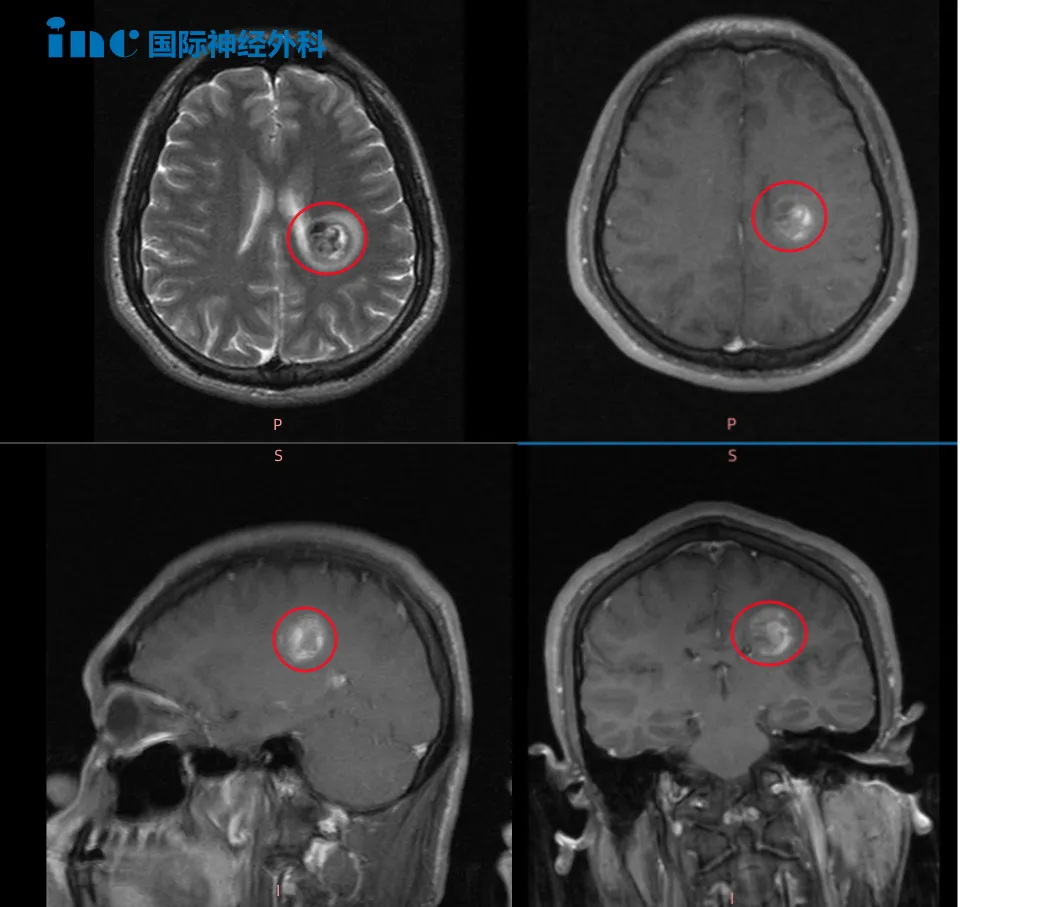

2022年5月MRI影像,血管畸形处于急性出血期

2023年3月手术前斌斌MRI影像

术前术后MRI影像对比